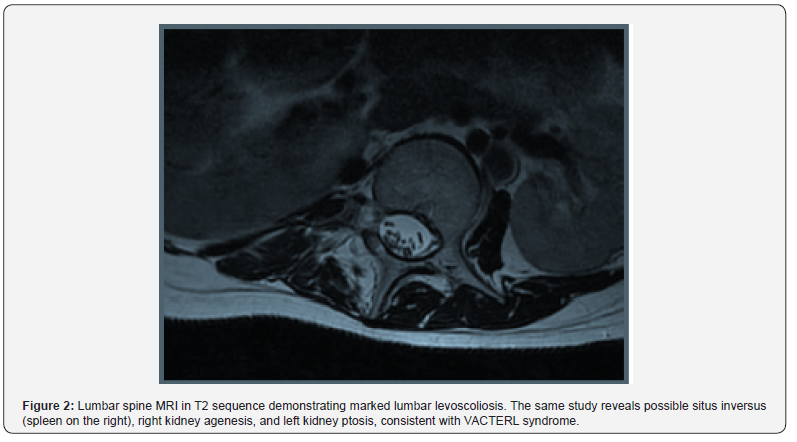

The procedure was uneventful, maintaining hemodynamic stability with a low-dose phenylephrine infusion (0.3-0.4mcg/kg/ min) and an intraoperative blood loss of 500 ml. Postoperative pain management included epidural boluses of 0.2% ropivacaine and 2mg of morphine chloride. The team paid special attention to positioning during surgery to mitigate the risk of respiratory compromise due to scoliosis. Fluid management was carefully adjusted to prevent fluid overload, given the patient’s single functional kidney. These measures contributed to a successful anesthetic outcome (Figure 2).